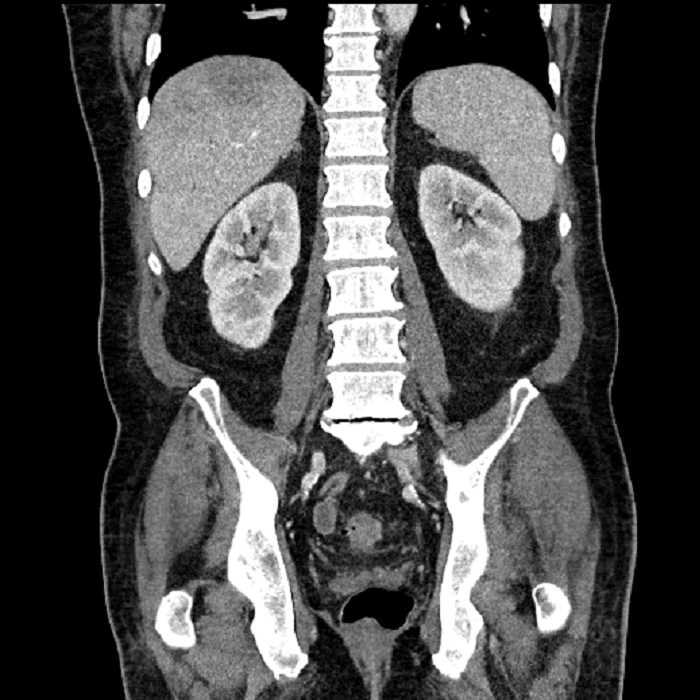

Age: 63

Sex: Male

Indication: Abdominal pain

• Large fluid density structure in hepatic segments 7 and 8 measuring 10 x 7 x 7 cm with internal septation and circumferential ill-defined low density compatible with edema

• Peripherally enhancing subcapsular collections along the anterior margin of the left hepatic lobe measuring 3 x 1 cm and 2 x 1 cm

• Clearly marginated fluid density structure in segment 7 and several other scattered tiny hypodensities, which likely represent cysts

• Hepatic abscess

Acute sigmoid diverticulitis complicated by a small contained perforation and a large abscess in the right hepatic lobe. Additional small subcapsular abscesses along the anterior margin of the left hepatic lobe.

• The classic CT imaging appearance is a double target sign with internal low density surrounded by an internal enhancing rim (capsule) and a low density external rim (edema)

• Abscesses may be unilocular or multilocular

• Gas is present in a minority of cases

• Unfortunately, necrotic tumors can have an overlapping imaging appearance, so it is important to follow these to resolution

Hepatic abscess showing the double target sign with low density internally surrounded by a thin inner enhancing rim (red arrow) and ill-defined outer low density rim (yellow arrow). Blue arrow indicates an internal septation. Red arrows: additional smaller subcapsular abscesses. Red arrow: focal contained perforation associated with diverticulitis.